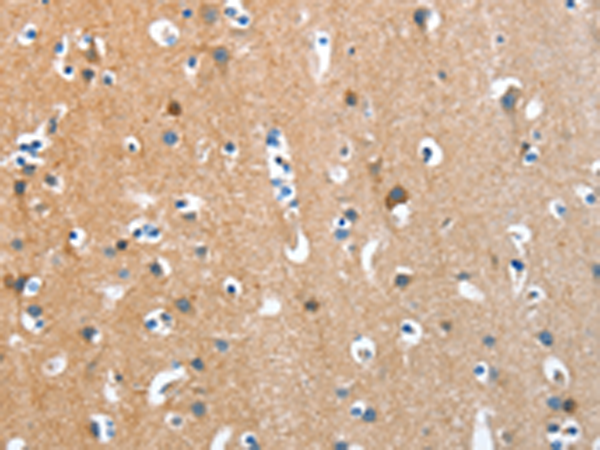

分类: 科研抗体货号: P07830别名: ACTA; ASMA; CFTD; MPFD; NEM1; NEM2; NEM3; CFTD1; CFTDM应用: WB,IHC反应种属: Human, Mouse, Rat